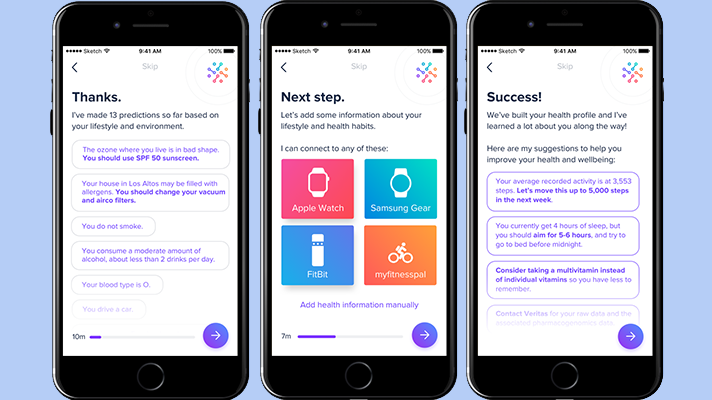

The doc.ai app plans to take one task away from doctors and give it to an artificial intelligence to interpret lab results. The company’s first product will interpret blood tests, then genetic tests, then they'll gradually add other kinds of tests.